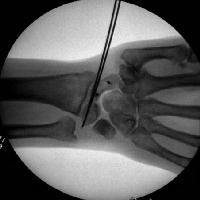

Intraoperative correction of scapholunate rotation using K-wires as joysticks on each bone.

Scapholunate pins and bone anchors - intraoperative fluoroscopy.

In this case, the scapholunate repair was stabilized with absorbable (Bionx) screws. Provisional fixation for two screws with a pin and a drill.

Click for larger image